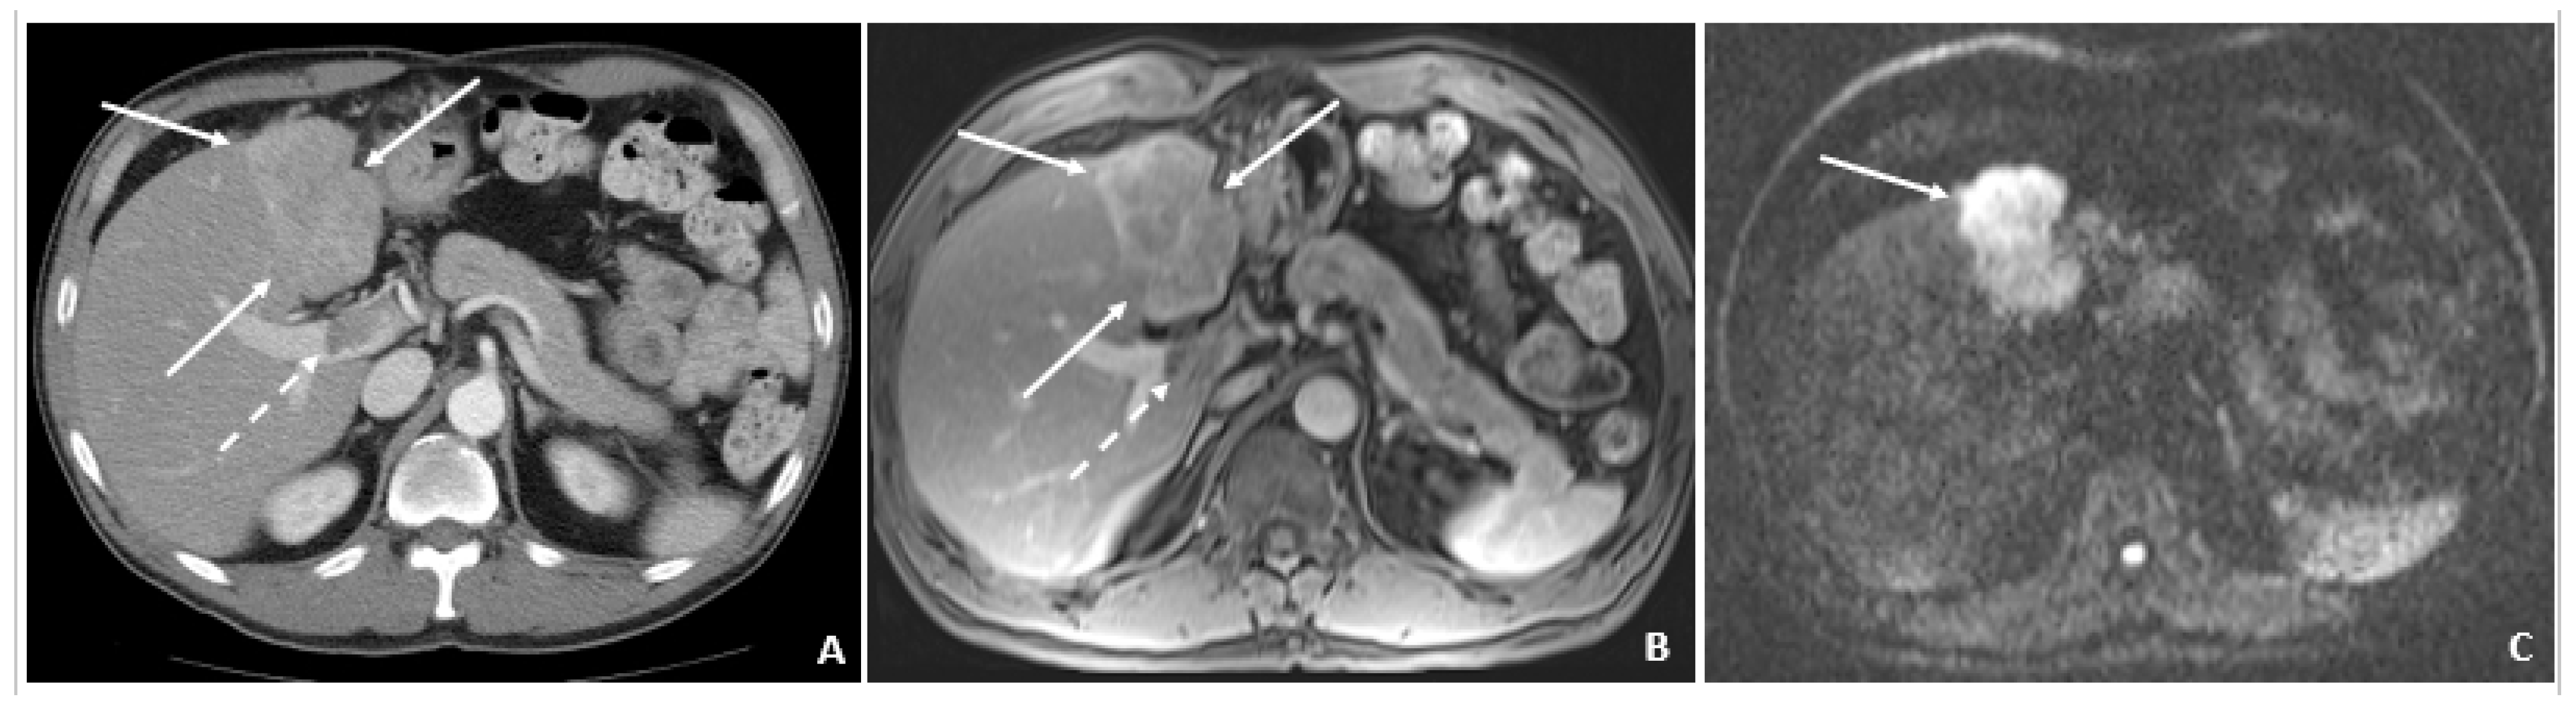

A 50-year-old male was diagnosed with CHB at age 40. With lamivudine treatment for 3 years, he achieved HbsAg seroconversion to anti-HBs and lamivudine was discontinued. Table 4 outlines his course. Five years later, on a follow up examination he was found to have HBV DNA 847 copies/mL, ALT 33 IU/L, and AFP 20.5 ng/mL. An MRI (December 2009) showed a 5 cm lesion consistent with HCC (Figure 1A,B). Repeat AFP was 17.8 ng/mL at time of HCC diagnosis, and AFP-L3% was 75.6. He underwent transarterial chemoembolization (TACE) with successful resolution (Figure 2A,B) and restarted lamivudine. The AFP remained at 3.0 ng/mL, and the MRI showed no evidence of HCC the following year. Two years after initial treatment, the AFP increased to 5.9 ng/mL with 57.5% L3. The MRI next month showed recurrent HCC at the treated site (Figure 3). The patient underwent laparoscopic radiofrequency ablation and therasphere treatment.

Figure 2.

Transarterial Chemoembolization (December 2009). (A) The selective left hepatic artery injection shows a blush of contrast corresponding to the hypervascular tumor (arrows). (B) An axial T1-weighted fat-suppressed portal-phase postcontrast MRI image 4 weeks following TACE shows lack of enhancement in the treated lesion with a small adjacent focus of necrosis (arrows).

Figure 3.

Recurrent HCC 2 Years Later (April 2011). (A) The contrast-enhanced CT image shows a hyperenhancing lesion in the left lobe (arrows) with adjacent tumor thrombus within the portal vein (dashed arrow). (B) The subsequent axial T1-weighted fat-suppressed postcontrast MRI image shows the lesion (arrows) to a slightly better advantage, along with the portal vein tumor thrombus (dashed arrow). (C) The diffusion-weighted image shows marked hyperintensity (arrow) within the left lobar mass, corresponding to diffusion restriction, typical of malignant tumors.